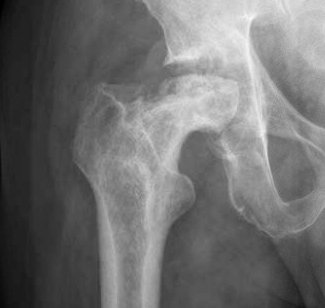

Osteonecrosis of the hip is a painful condition that occurs when the blood supply to the bone is disrupted. Because bone cells die without a blood supply, osteonecrosis can ultimately lead to destruction of the hip joint and arthritis. Osteonecrosis is also called avascular necrosis or aseptic necrosis. Although it can occur in any bone, osteonecrosis most often affects the hip. More than 20,000 people each year enter hospitals for treatment of osteonecrosis of the hip. In many cases, both hips are affected by the disease.

The hip is a ball-and-socket joint. The socket is formed by the acetabulum, which is part of the large pelvis bone. The ball is the femoral head, which is the upper end of the femur (thighbone). A slippery tissue called articular cartilage covers the surface of the ball and the socket. It creates a smooth, low friction surface that helps the bones glide easily across each other.